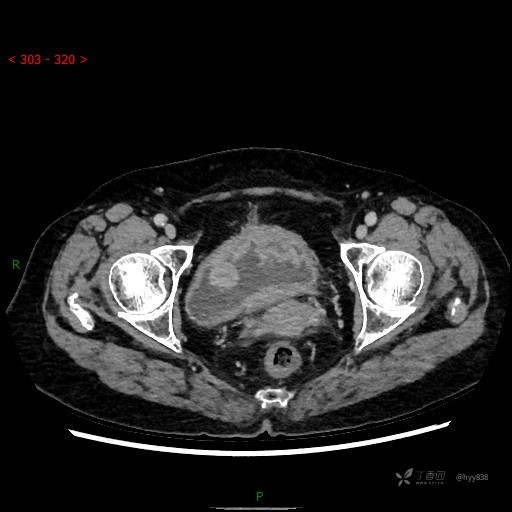

膀胱少见肿瘤,欢迎挑战---结果公布~

华夏览雄 达人已点赞患者性别:女

患者年龄:73岁

主诉:肉眼血尿3周

简要病史:患者诉3周前无明显诱因开始出现肉眼血尿,发作时尿液呈鲜红色,为全程血尿,无明显血凝块;伴小腹胀痛,无尿频、尿急、尿痛;无寒战、发热;无恶心、呕吐,就诊于当地医院行输液治疗后,出现不规则血凝块,进一步完善相关检查提示膀胱占位,活检提示膀胱炎性改变,现患者为进一步治疗,遂来我院,门诊以“膀胱肿物”为主诉入院。 起病以来,患者精神、饮食、睡眠稍差,大便如常,小便如上述,近期体力、重无明显变化

临床诊断:膀胱肿瘤

膀胱CT平扫(2022.10.20)

增强(2022.11.1)